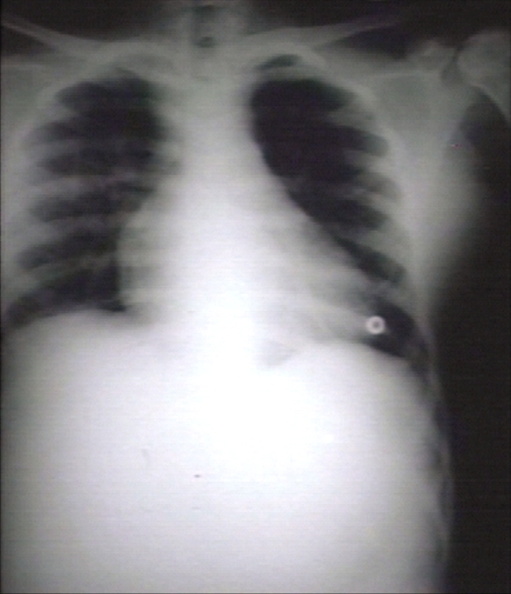

RADIOLOGY: LUNG: SICKLE CELL DISEASE: ACUTE PULMONARY CRISIS: CHEST X-RAY; SHOWS CARDIOMEGALY AND INCREASED PULMONARY MARKINGS IN ACUTE PULMONARY CRISIS. AUTHORS ARE BE AND RV (PLAIN FILM)